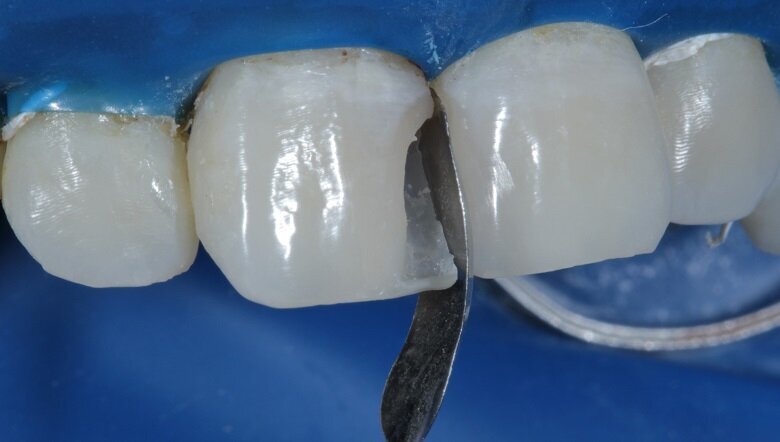

Fig 13: Band Placed (Sectional Matrix)

Fig 14: Proximal View of band placed

A sectional matrix was then placed in between the teeth (Fig 13). Proximal view of the same depicts that the band was placed and adapted in a manner to achieve tight contacts without overhangs (Fig 14). A proximal wall was built with the help of this band with A2 enamel shade (Fig 15). On this shell, A2 dentin layer was added to give the internal anatomy (Fig 16).